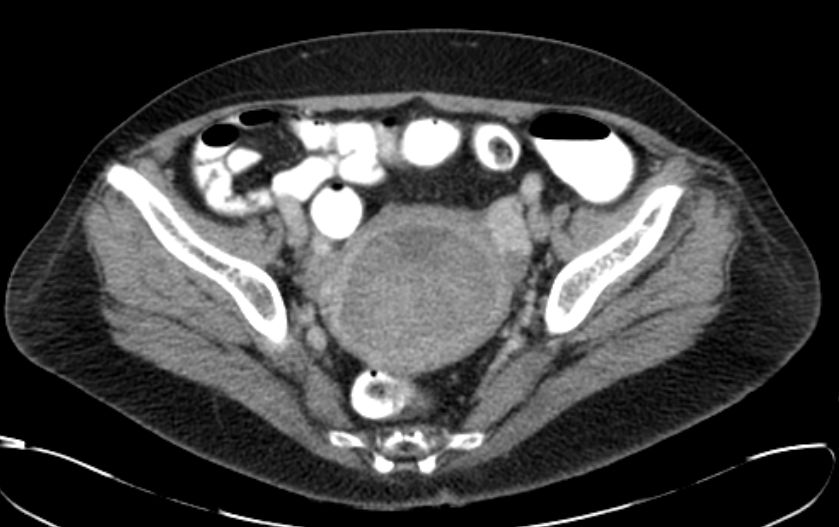

69-jährige Frau, die vor 4 Jahren ein Mammakarzinom hatte und adjuvant mit Anastrozol behandelt wird.

Wegen PM-Blutung wurde eine Abrasio durchgeführt, die einen malignen Müllerschen Mischtumor des Endometriums ergab.![]() |

Postoperatives Stadium pT1a (beginnende Wandinfiltration) pNo Mo Lo Vo Ro![]() | |